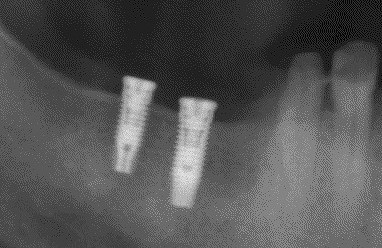

インプラントの術前・術後 Kさん